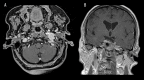

Case report: We report the endovascular approach to three patients harboring glomus jugulare paragangliomas. In all cases incomplete occlusion of the lesions was achieved and recanalization in the follow-up period was revealed. Two patients presented no clinical improvement and the remaining one experienced a transient withdrawal of tinnitus.

Conclusions: It is technically difficult to achieve complete obliteration of glomus jugulare tumors with the use of embolization and the subtotal occlusion poses a high risk of revascularization and is not beneficial in terms of alleviating clinical symptoms.